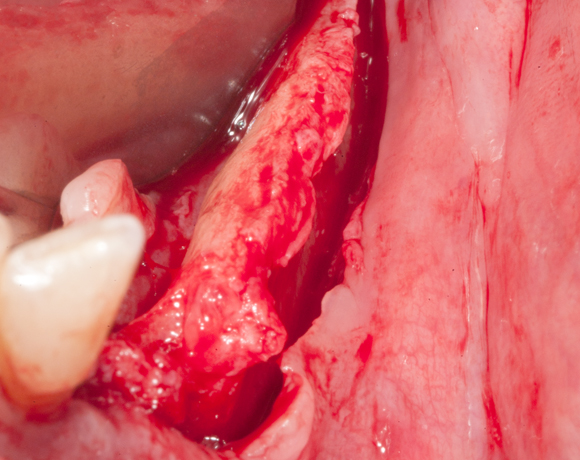

Die Knochenspaltung auch Bonesplitting genannt, ist eine geeignete Möglichkeit im Unterkieferseitenzahnbereich Knochen aufzubauen, um Implanate setzen zu können. Vorraussetzung ist eine ausreichende Knochenhöhe.

Lösung entschieden. Nachdem die endodontisch behandelten Zähne 32 und 33, die mit VMK – Kronen

und Geschiebe versorgt waren, abgebrochen sind, war die Patientin für den Eingriff mit Knochen-